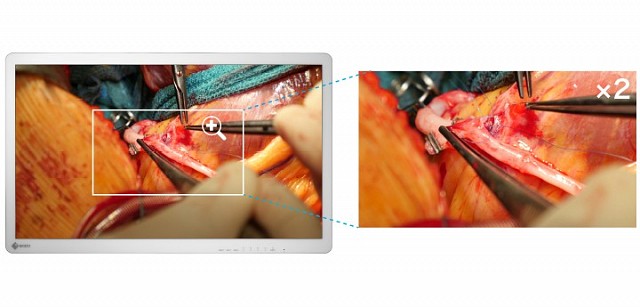

- 具有稀疏编码(SRSC)的智能分辨率,可显示高清影像

EX3241具有4K UHD(3840 x 2160像素)分辨率和高亮度的32英寸宽屏手术监视器。